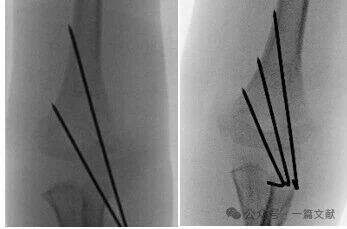

K-Wire Fixation Techniques:

* Lateral-Only Pinning:

* Most commonly used technique.

* Can utilize 2 or 3 laterally placed K-wires.

* Cross Pinning (Medial & Lateral):

* Provides biomechanical stability.

* Carries a risk of iatrogenic ulnar nerve injury.

* All-Lateral Pinning (divergent):

* Carries a risk of radial nerve injury.

* Less commonly used.

* Ideal Pin Placement Requirements: Use 1.5-2 mm K-wires. Pins should engage the medial and lateral columns with a divergent pattern. Greater separation between pins increases stability. As shown in the figure, pin configurations for Type 2A, 2B, and 3 fractures.

* Achieve wide separation at the fracture site.

* Pins should follow the metaphyseal flare to capture the lateral column.

* Laterally placed pins can be used to capture the medial column.

* Pin tips should engage the distal fragment just proximal to the fracture line.

* A third pin can be added between the two main pins for additional stability.